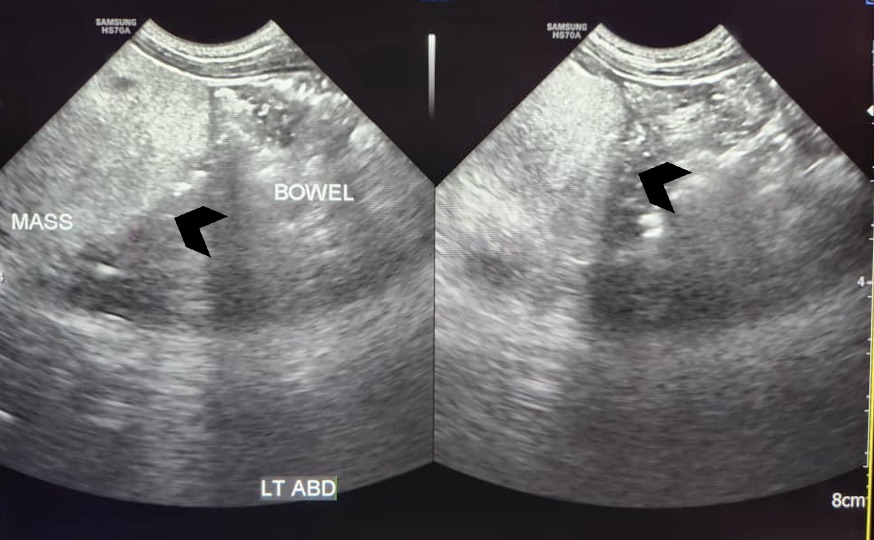

Lipoblastoma accounts for 5-30% of paediatric soft-tissue tumours. It is a rare tumour originating from embryonic fat cells, mainly affecting infants and young children. While it is commonly found in the extremities, it can occur anywhere in the body. We reported a case of a 2-year-old boy with mesenteric lipoblastoma presenting with a 3-month history of abdominal distension and discomfort. Computed tomography (CT) scans of the thorax, abdomen, and pelvis revealed a large lobulated intraabdominal mass with fat components, diagnosed as mesenteric lipoblastoma. The patient underwent successful laparotomy, tumour excision, bowel resection and primary anastomosis. Histopathology confirmed the diagnosis of lipoblastoma. Post-operative recovery was uneventful.